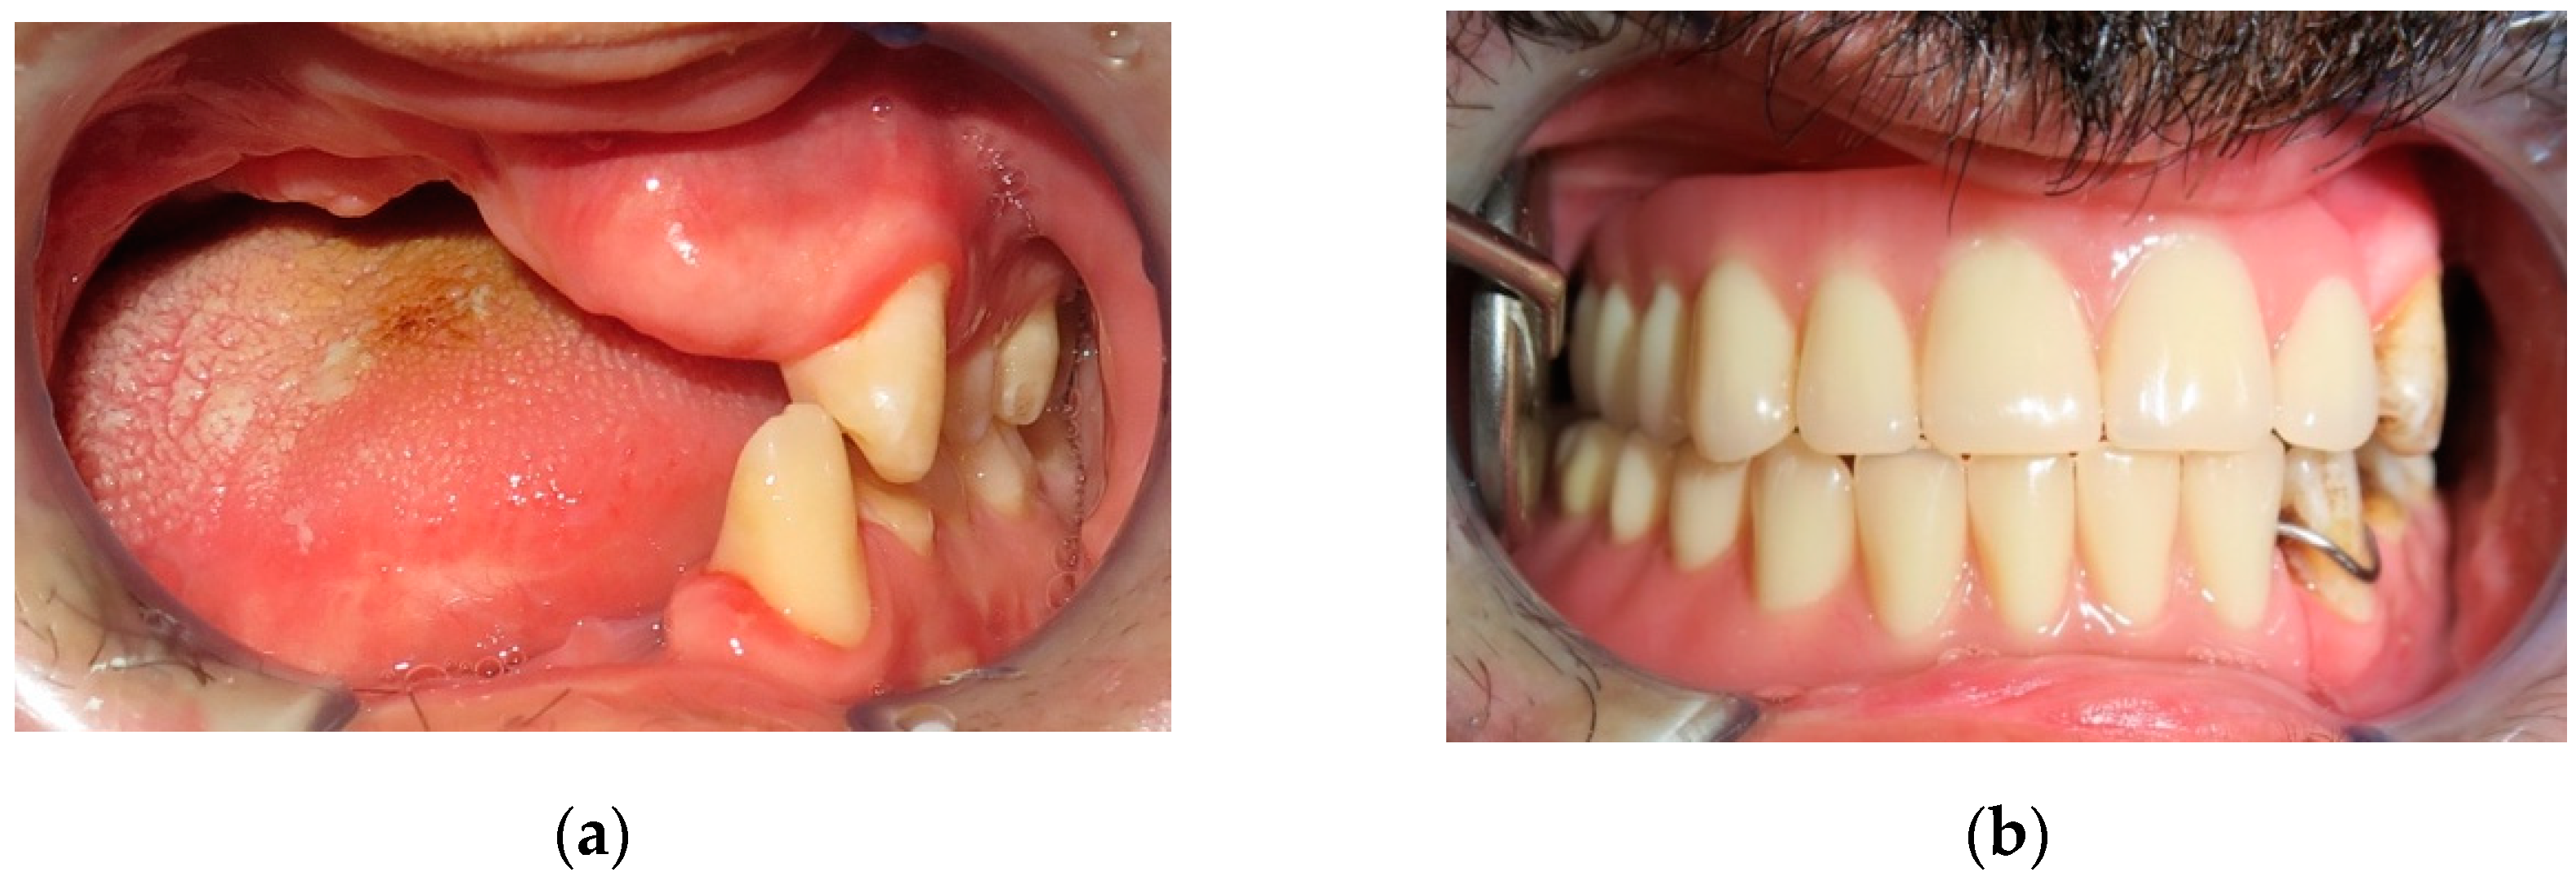

| 1 | 22/M | High-velocity injury | T4, Lower maxilla, Basal bone, Gingival tissue and Soft tissue | Emimandibulectomy dx | Free Fibula Flap | Fixed implant-supported prosthesis (n. 5 dental implants) |

| 3 | 29/M | High-velocity injury | T4, Upper maxilla, Basal bone, Gingival tissue and Soft tissue | Emimaxillectomy dx | Free Fibula Flap | Fixed implant-supported prosthesis (n. 6 dental implants) |

| 4 | 31/M | High-velocity injury | T4, Upper and Lower maxilla, alveolar bone, Gingival and Soft tissue | Alveolar Resection, I quad. + IV quad. | Free Iliac Crest Flap | Fixed implant-supported prosthesis (n. 10 dental implants) |